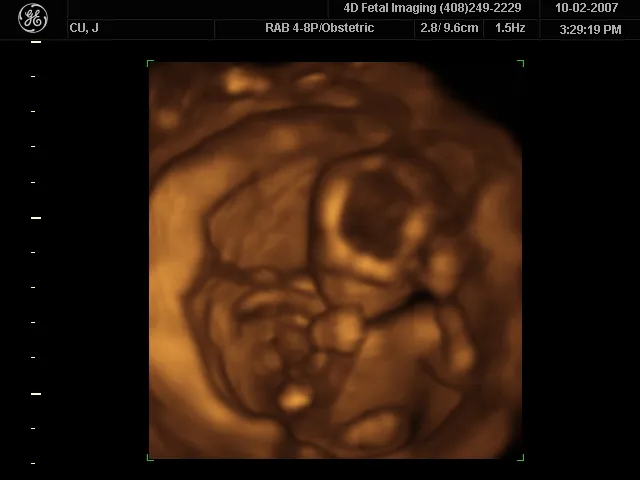

How much detail can ultrasound reveal? The image in Figure 17.47 is typical of low-cost systems, but that in Figure 17.48 shows the remarkable detail possible with more advanced systems, including 3D imaging. Ultrasound today is commonly used in prenatal care. Such imaging can be used to see if the fetus is developing at a normal rate, and help in the determination of serious problems early in the pregnancy. Ultrasound is also in wide use to image the chambers of the heart and the flow of blood within the beating heart, using the Doppler effect (echocardiology).

This is an image of a 3D ultrasound scan of the fetus showing an unborn baby sucking its thumb.

Figure 17.48 A 3D ultrasound image of a fetus. As well as for the detection of any abnormalities, such scans have also been shown to be useful for strengthening the emotional bonding between parents and their unborn child. (credit: Jennie Cu, Wikimedia Commons)